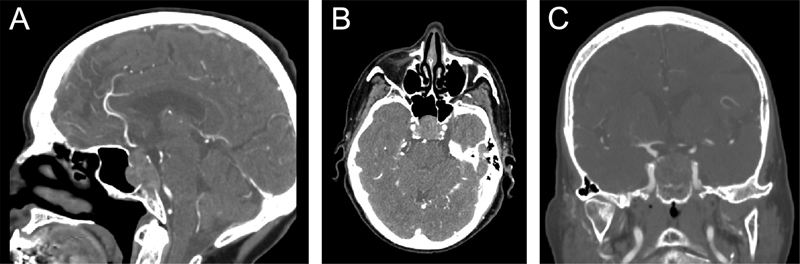

Introduction  Clival tumors are rare and heterogeneous. Although some benign prototypical sellar lesions may present as clival tumors, the likelihood of malignant disease is higher. Here we define a novel algorithm for the workup and management of clival masses through an illustrative case of colorectal adenocarcinoma metastasis to the clivus. Methods  In this case report, the best practice guidelines for managing clival masses are described through a literature review and refined by senior author consensus. We conducted a focused systematic review to characterize the present case in the context of clival metastasis from gastrointestinal malignancy. Results  An 83-year-old woman presented with 4 weeks of headaches and blurry vision. Examination revealed partial right abducens and left oculomotor palsies. Magnetic resonance imaging (MRI) identified a large, weakly enhancing sellar and clival mass with sphenoid sinus extension. An aggressive subtotal endoscopic endonasal resection was performed with removal of all sphenoid, clival, and sellar disease without cavernous sinus wall resection. Pathology confirmed colorectal adenocarcinoma; computed tomography (CT) imaging identified an ascending colon mass with metastases to the liver and mesenteric nodes. Palliative oncologic therapies were recommended, but she elected hospice, and died 3 months after initial presentation. Gastrointestinal clival metastases are exceedingly rare among sellar and clival pathologies, with eight prior cases reported, most of which presented with diplopia from abducens nerve involvement. Conclusion  Clival masses are uncommon skull base lesions that are associated with more aggressive diseases. We present a consolidated framework for decision-making in these challenging patients, alongside an unusual case example that illustrates the importance of increased suspicion for malignant clinical entities in this setting.